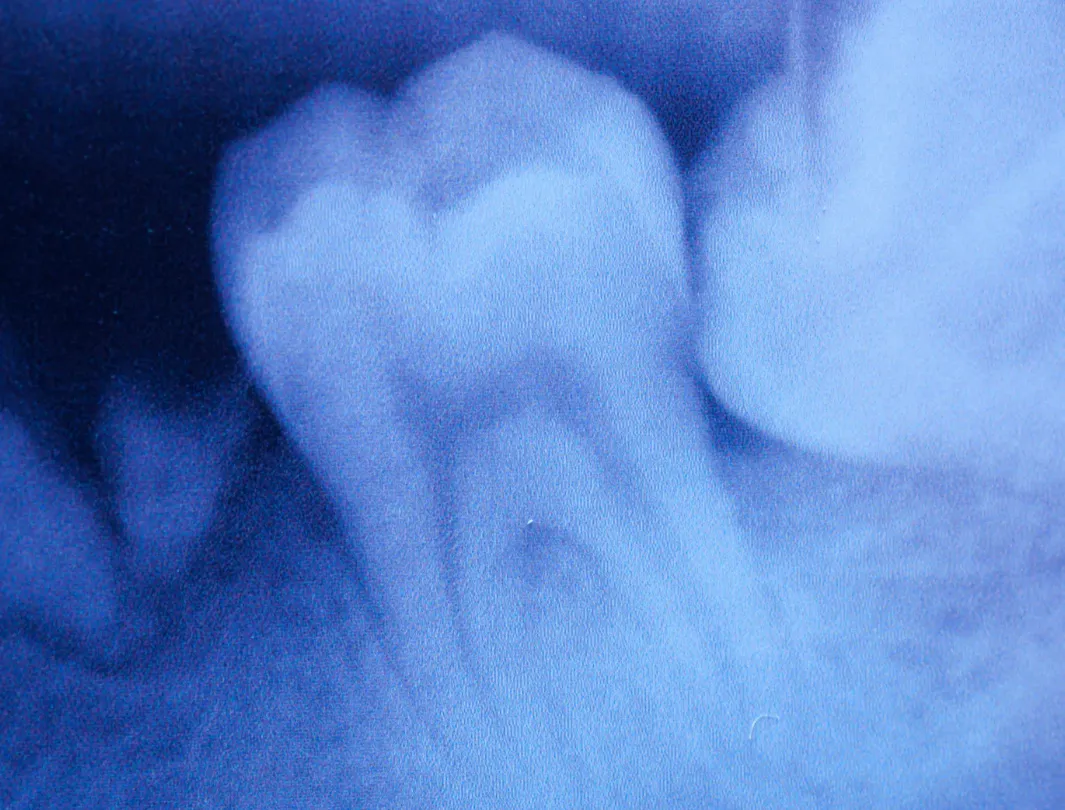

- Diagnostik: Röntgenbilder, DVT (3D-Scan) zur exakten Analyse